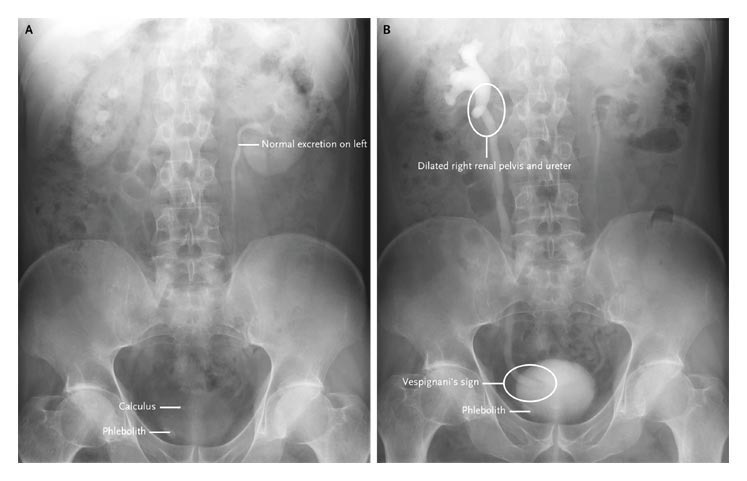

Then showed delayed excretion of the contrast material by the right kidney, a dilated right renal pelvis and ureter to the bladder, and a filling defect around the ureteric meatus at 12 minutes after injection (Panel B). The findings are related to edema due to the passage of a calculus.

These findings are most suggestive of a calculus at the right uretero-vesical junction.